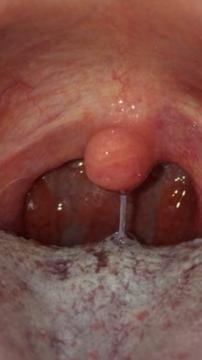

Dobry deň už som strašne zufaly a tak preto sa obracam na vás..Mam neskutočne bolesti hrdla hlavne keď prehltam.Mam v hrdle ako su diery do nosa take krvave vačky a nemiznu mi ...bol som u doktora a dal mi antibiotika Azithromycin a nezaberaju..pošlen vam aj fotku a budem velmi vdačny ak mi pomôžete .... Ďakujem pekne... Pošlem vam aj fotku

Dobrý deň, mandle sú zvačené a prekrvené. Antibiotika zrejme nezabrali, neviem, či Vám lekár urobil výtez z krku, každopádně, na mandliach sa často usídľuje streptokok a najlepšie antibotikum stále zostaáva penicilín. Doporučila by som zmenu antibiotik (prípadne ešte předtím výter z krku)na penicilín - už po 2-3 dávkách sa Vám musí uĺaviť od bolesti a mandle sa začnú zmenšovať. Ak by stav trval aj po penicilíne, doporučujem návštěvu ORL lekára.

Ale ja už nemam mandle vybrali mi ich to su tam take vačky krvave....môže to byť chronicky zapal hrdla?